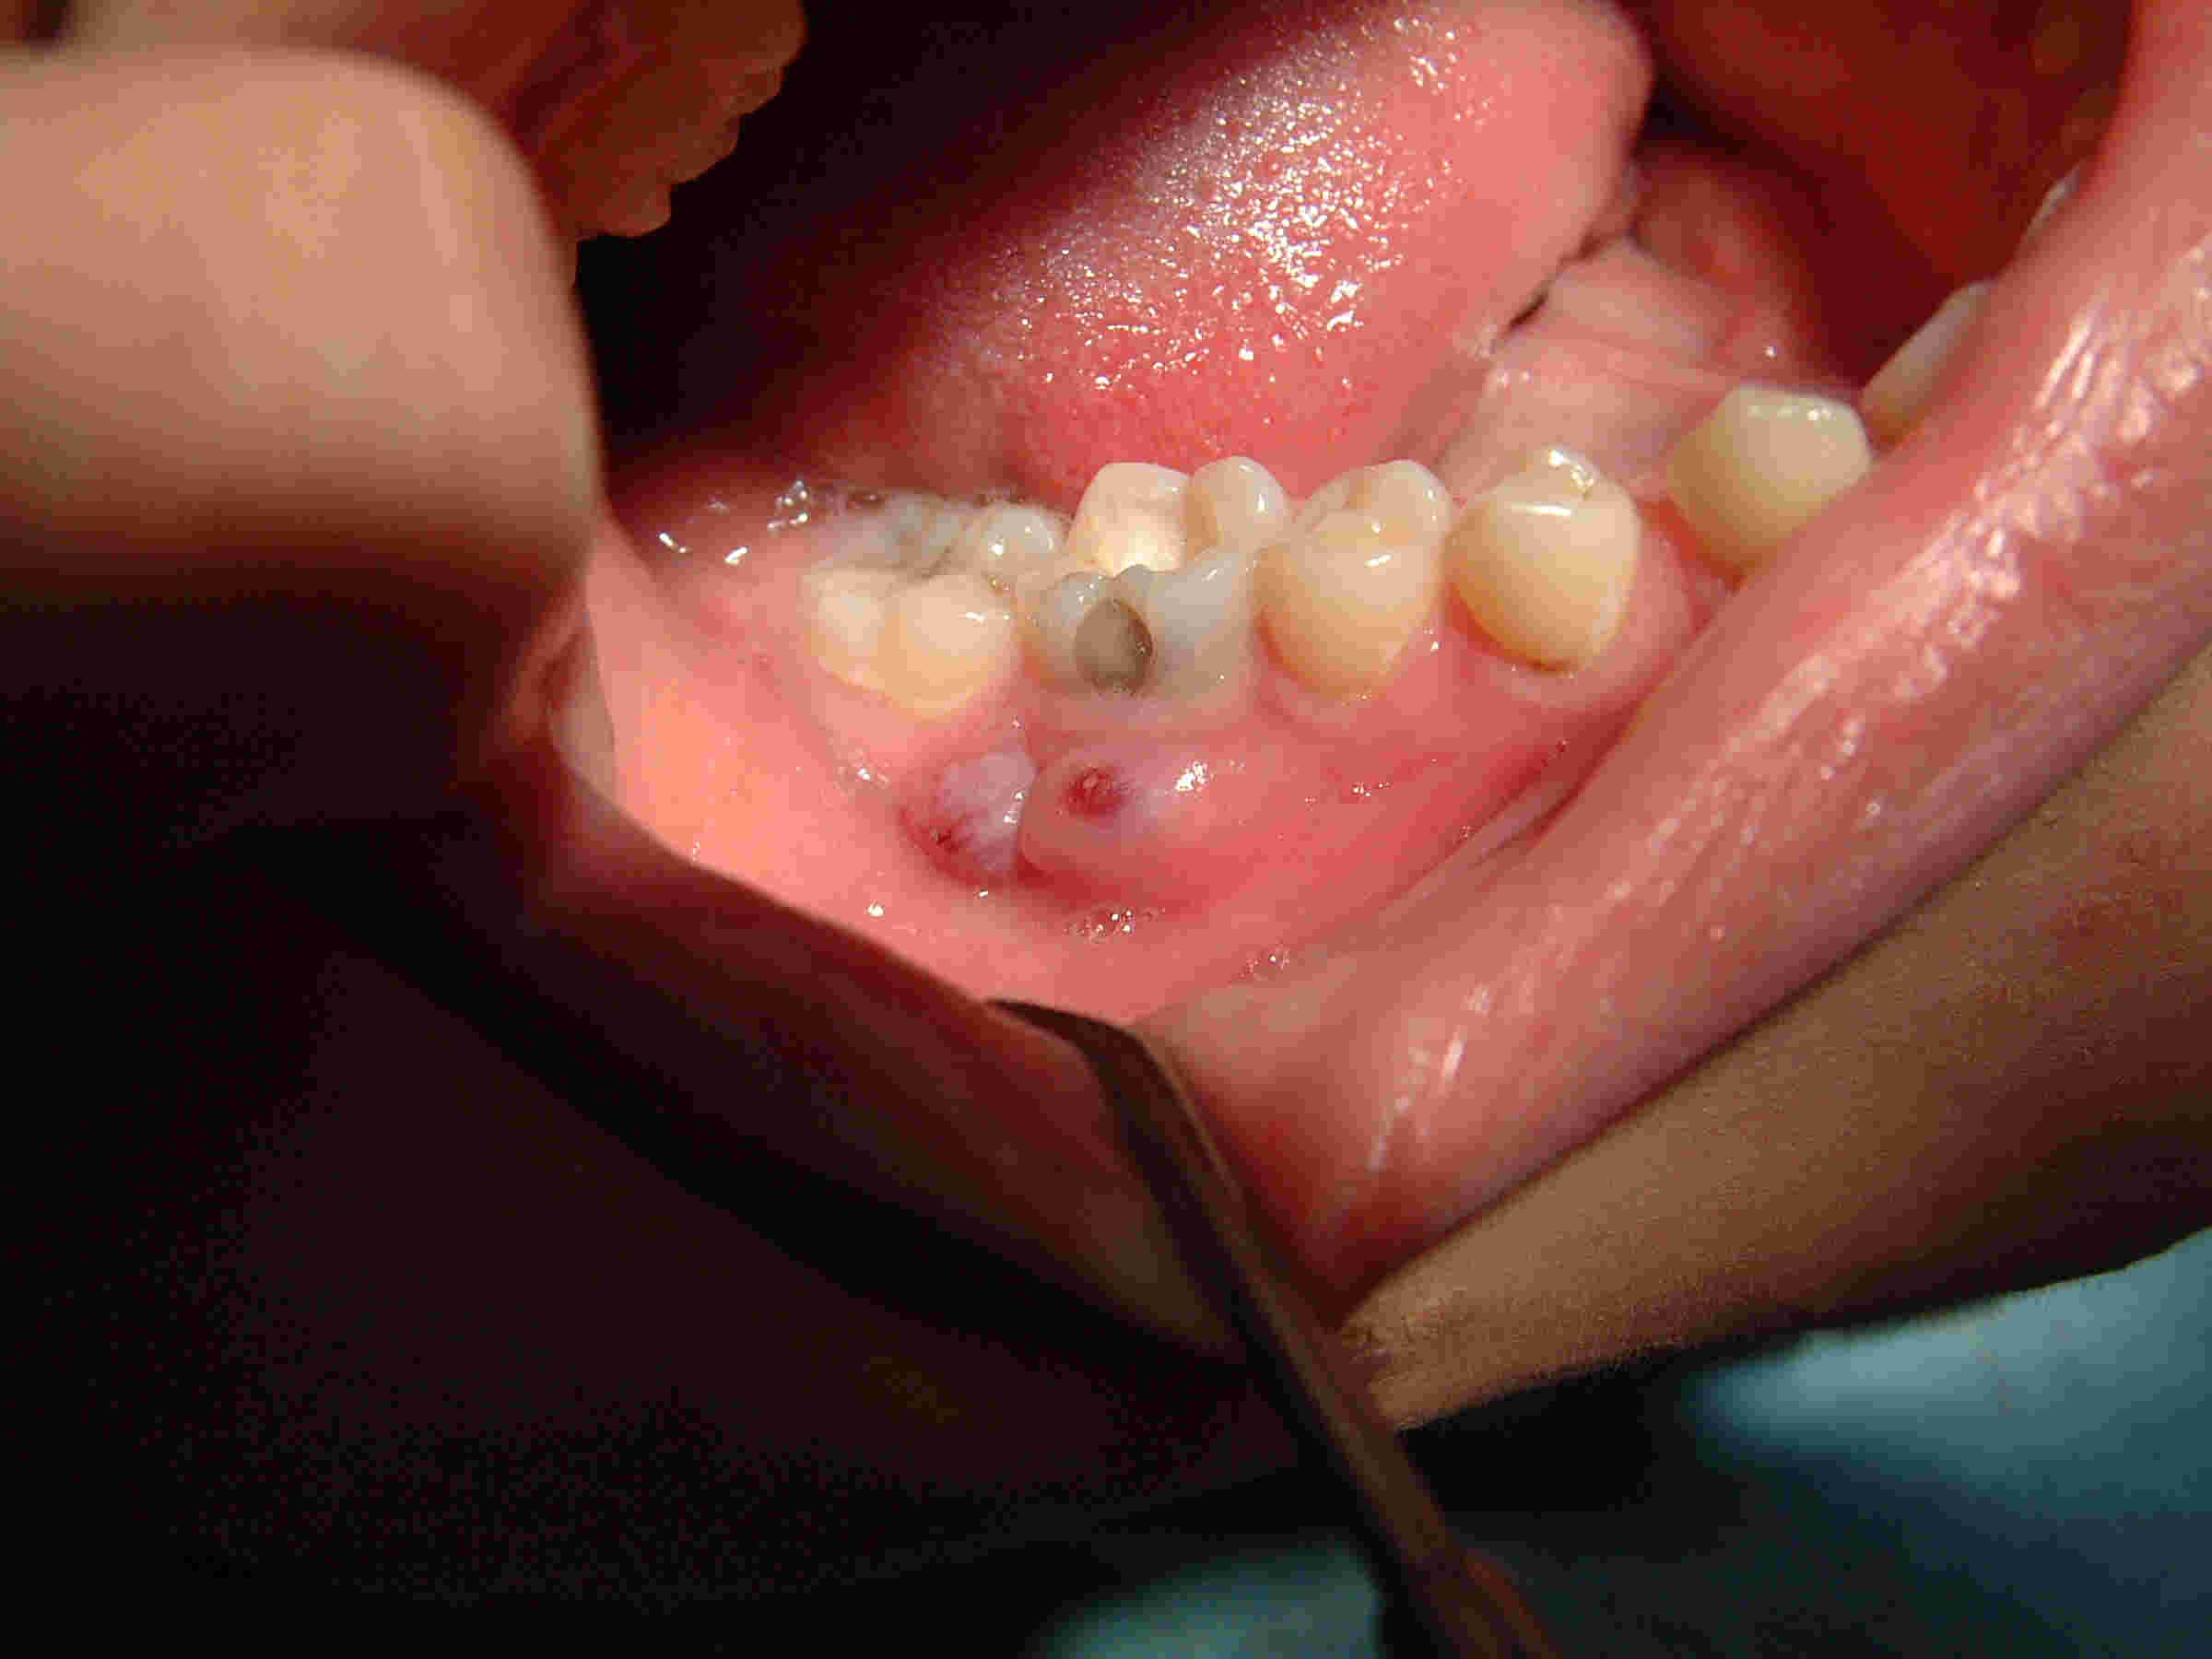

Die 16jährige Patientin stellte sich mit einem stark klopfempfindlichen Zahn 46 mit vestibulärer Schwellung über der mesialen und Fistelung über der distalen Wurzel vor. Die Fistel mündete in einer das Fistelmaul umwuchernden blumenkohlartigen Schwellung, wie sie nicht untypisch für eine lange Fistelanamnese ist.

Klinisches Bild bei der Erstuntersuchung, unmittelbar nach Trepanation, Abszesseröffnung mittels Sonde und Aufbereitung (Klick!)